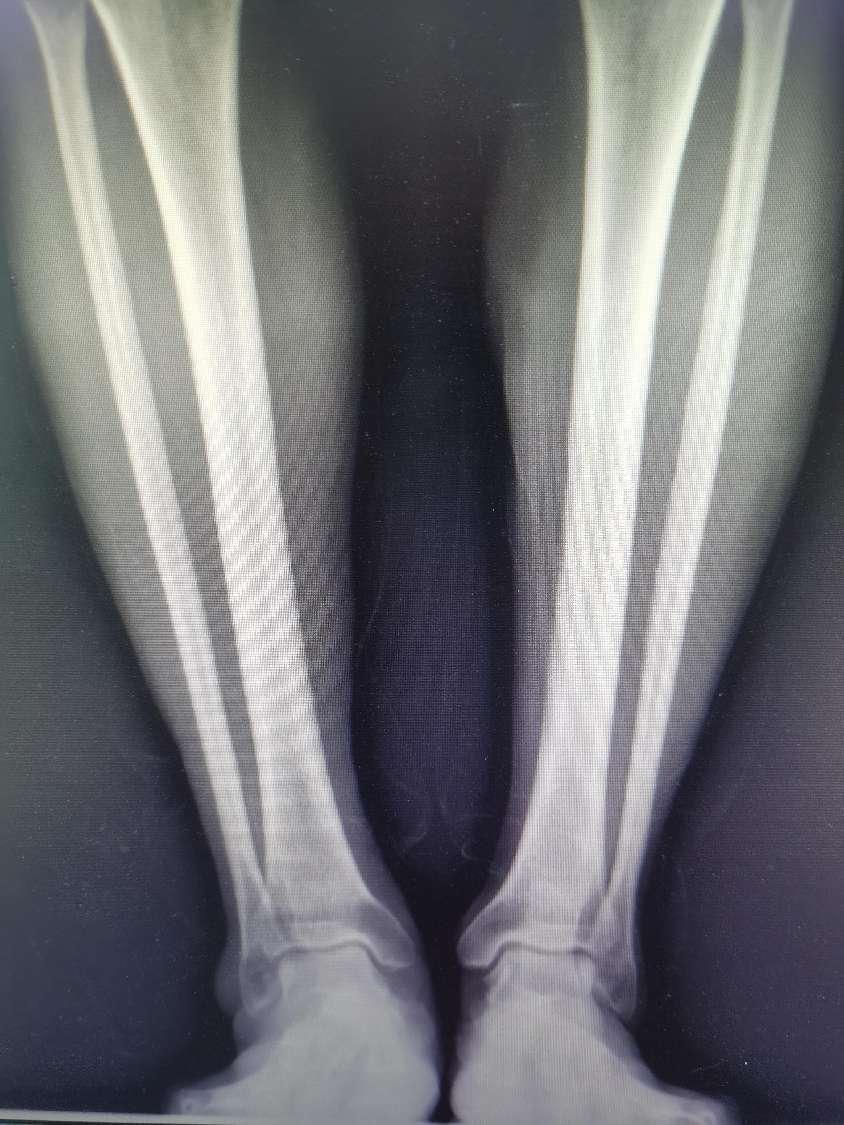

患者,男性,59岁,两年前开始出现右侧踝关节肿痛伴活动受限,以劳累后或长距离行走表现明显,疼痛逐渐加重,曾行“关节镜下右侧踝关节滑膜清理,增生骨赘切除术”,术后改善不明显,为进一步行踝关节置换术门诊入院。

术后X线检查